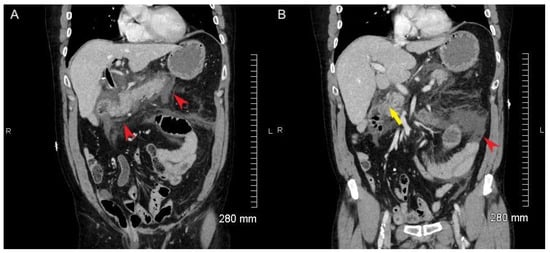

A 67-year-old man underwent surgery for repair of an inguinal hernia. The clinical history of the patient included a surgical intervention after a traffic accident more than 40 years ago but was otherwise unremarkable. Due to complications, a laparotomy was necessary, and a postoperative CT was performed. A small bowel obstruction was ruled out, but the CT revealed multiple space-occupying lesions in the abdomen and pelvis with contrast enhancement. No visceral or bone lesions were identified. No spleen was present.

Initially, a malignant disease, particularly a lymphoma, was suspected, and magnetic resonance imaging (MRI) of the abdomen was performed for further evaluation. This confirmed the partially lobulated, well-defined lesions (Figure 1). In view of the previous surgery and the missing spleen, the differential diagnosis of multilocular ectopic splenic tissue (splenosis) was considered. 3. PET/CT ImagingTo avoid further interventions, a PET/CT with [68Ga]Ga-oxine-labeled RBCs was performed. Synthesis of [68Ga]Ga-oxine and RBC labeling procedures were adapted from [6,7]. A total of 8 mL of venous blood was taken from the patient in 2 mL of citrate anticoagulant buffer. The RBCs were separated from the plasma via centrifugation and heated to 48 °C for 10 min in order to induce heat denaturation and labeling with [68Ga]Ga-oxine. After three washing cycles with 0.9% saline, the labeled RBCs were resuspended. RBCs containing 188 MBq [68Ga]Ga-oxine were reinjected intravenously.

All abdominal and pelvic masses showed a high tracer uptake increasing over time (Figure 2), with the highest uptake values measured in the subhepatic index lesion (Figure 1 and Figure 2, arrows): SUVmean: 69.1/94.1 at 10/25 min after tracer injection, respectively, showing an increase of 36% between the two time points. During the same interval, blood pool activity decreased (SUVmean: 9.6/6.8, −29%), indicating the removal of the labeled, heat-damaged RBCs from the blood by the functioning splenic tissue. The diagnosis of disseminated splenosis was confirmed. Since no symptoms were present and there was no evidence of an increased susceptibility to infections, no further treatment was necessary. 4. Discussion